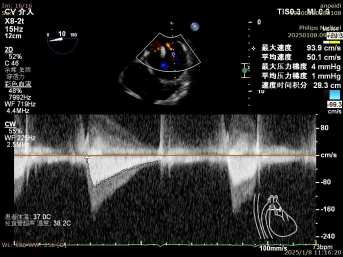

一切准备就绪后,麻醉手术中心专家凭借精湛技艺,让患者全程处于平稳麻醉状态,为手术筑牢安全根基。超声诊断科医生犹如“透视眼”,实时提供精准影像指引,让手术操作有的放矢。术中,陈玺全副主任团队在2区植入一枚长宽夹后,棘手状况再现。由于瓣叶张力过大,团队果断调整策略,以特定角度释放二尖瓣夹。当夹子关闭至-30°时,奇迹发生,反流降至1+,术后跨瓣压差仅为1mmHg,手术效果惊艳众人。